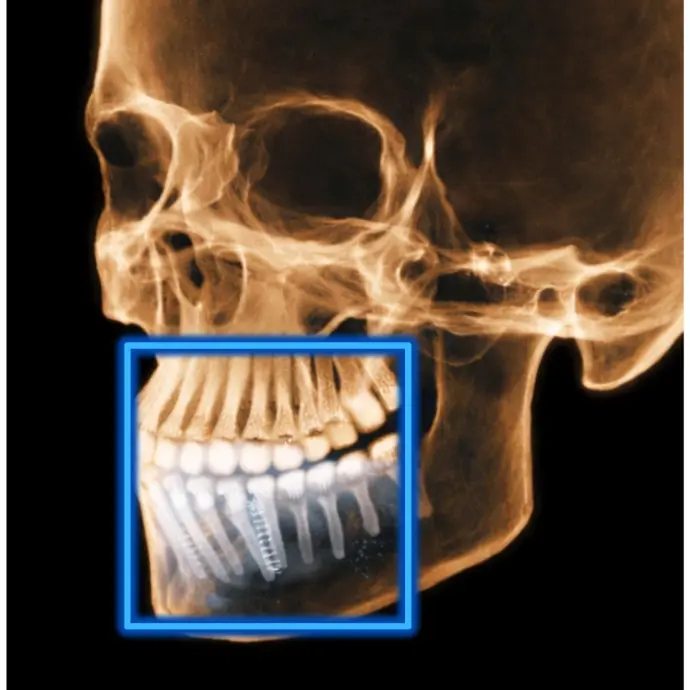

TOMOGRAFÍA DE IMPLANTES

Cuando es necesario evaluar las condiciones óseas de los rebordes alveolares.